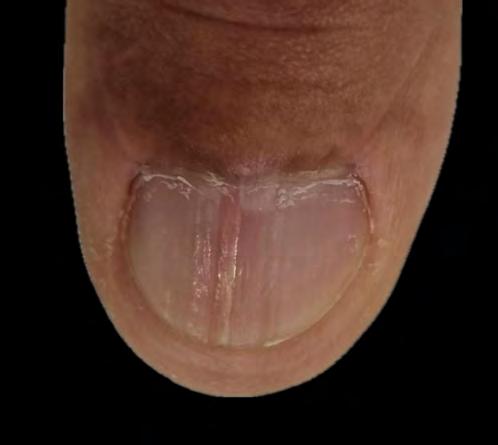

Onicomatricoma - sempre um desafio diagnóstico

Soraya Neves Marques Barbosa dos Santos, Sílvia Iovine Kobata, Isabela Boechat Morato, Natália de Paiva Sobreira